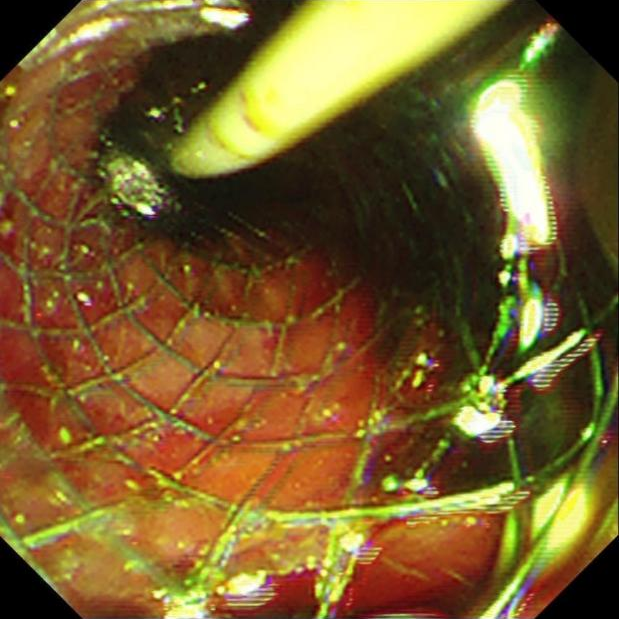

老家四川的小张(化名)是一名肺癌晚期患者,2023年10月,小张出现头晕,无法直线行走的情况,时间一长头晕的症状逐渐加重。 10月13日,小张在中国医学科学院肿瘤医院深圳医院的检查结果提示:脑膜转移。对应治疗后症状有所缓解。 11月16日,小张出现皮肤、巩膜发黄,抽血检验提示胆红素进行性升高,考虑为梗阻性黄疸。 胆总管是胆汁唯一的出路,当胆总管出现梗阻时,胆汁没有排出的通道,就会出现腹痛、发热、黄疸等情况。 这条“生命通道”一旦被完全堵死,极易发展为化脓性胆管炎、感染性休克、脓毒血症等情况,随时危及生命。 该技术是目前微创治疗胆胰疾病的主要手段之一,整个手术耗时仅40分钟。术后复查,小张胆红素指标明显下降。 ERCP技术具有创伤小,病程短,疗效好,并发症少等优点,目前医院已能熟练开展该项技术,内镜科也在解决胆道、胰腺系统急危重症方面有了新的突破,为患有胆胰系统疾病的患者带来福音。 内镜逆行胰胆管造影术(ERCP)是指医生将十二指肠镜经口插至十二指肠降部,找到十二指肠乳头,经十二指肠乳头导入专用器械进入胆管或胰管内,在X线透视或摄片下注射显影剂造影、导入经口胰胆镜/超声微探头观察、进行胆管刷检/活检获取病理标本等操作,完成对胆胰系统疾病的诊断,并在诊断的基础上实施相应介入治疗技术的总称,是国际公认的胆道、胰腺系统疾病诊断的金标准。 胆道梗阻引起的黄疸 临床实验室或影像学检查,支持胰腺或者胆道的疾病,包括结石、肿瘤、硬化性胆管炎等 胰腺相关疾病,包括胰腺肿瘤、慢性胰腺炎、胰腺脓肿等 原因不明的胰腺炎 奥迪氏括约肌病变 胰管或者胆管的组织活检 内镜下逆行胰胆管造影术、内镜下鼻胆管引流术、内镜下乳头括约肌切开术、内镜下胆管支架植入术、内镜下胰管支架植入术、内镜下胆管结石取石术、内镜下胆管扩张术、内镜下乳头括约肌球囊扩张术等。 以上ERCP技术,可满足梗阻性黄疸、胆道结石、胆管/胰管狭窄等常见胆胰系统疾病的诊治。